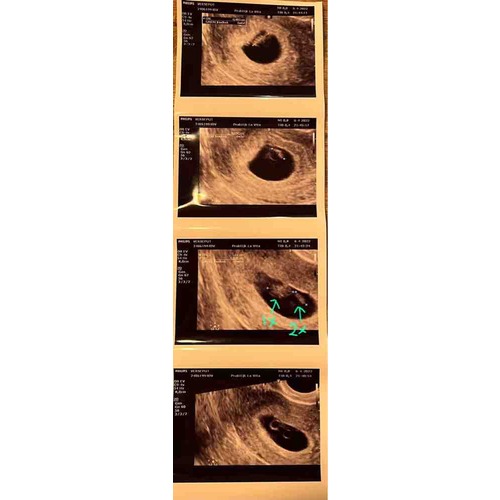

Ze zijn nu ongeveer 5,5 week, met 5 weken heb ik een echo gehad. Ik dacht verder te zijn en had om medische redenen een vroege echo nodig.

Helaas was er op die echo nog geen hartactie te zien, maar wel twee even grote vruchtzakjes met dooiers.

Over anderhalve week terug om te kijken hoe ze het doen 馃崁